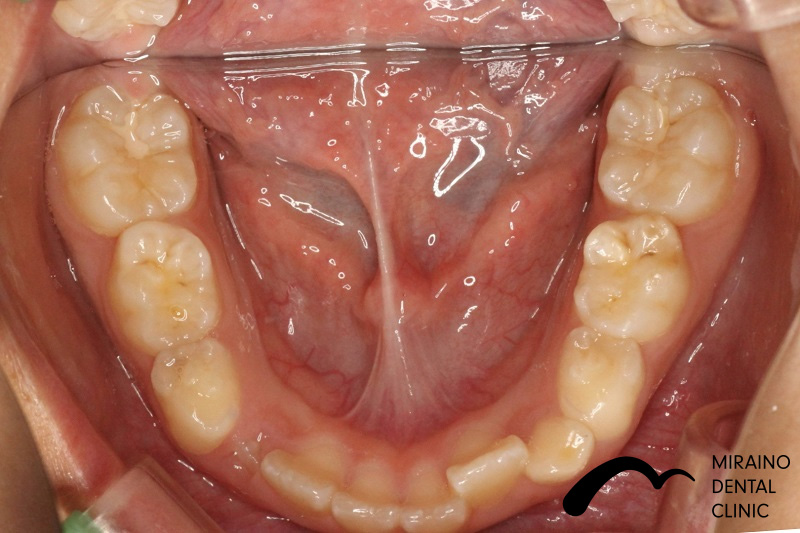

過蓋咬合①

| 施術名 | マウスピース矯正(インビザライン) |

| 施術の内容 | 歯科矯正でも目立ちにくい新しい矯正方法です。 透明に近いマウスピース型の矯正装置(アライナー)のため、歯に装着しても目立つことなく歯並びを矯正することが出来ます。 また、一人ひとりの合わせて矯正装置を作製いたします |

| 治療費 | インビザライン990,000円 |

| 考えられるリスク、副作用 | 疼痛・咬合時痛を生じる事があります。時間経過とともに治ります。 |

| 考えられるリスク、副作用[矯正] | 継続使用により緩んだり、外れやすくなる事があります。 割れたり壊れたりする事があります。諸々の事情により、治療期間が当初よりも伸びる事があります。 所定の装着時間22時間を守って頂けない場合、治療計画どおりに治らない可能性があります。 歯が動く際に、痛みが出る事があります。 矯正期間中は虫歯や歯周病のリスクが高まりますので、しっかりとしたケアが必要です。 歯の移動に伴う歯肉退縮や歯根吸収が起こる事があります。 インビザライン・システム(invisalignR)は、アメリカのアラインテクノロジー社より提供されている、カスタムメイドの矯正装置ならびに、これを用いた治療システムを指します。 インビザラインを用いた治療は保険適用外の自由診療となります。 厚労省の認可(医薬品医療機器等法上の承認)は得ていないため、まだ明らかになっていないリスクが存在する可能性があることをご了承ください。 |

| 全て | 必ずしもご希望通りの見た目にならない事があります。 |